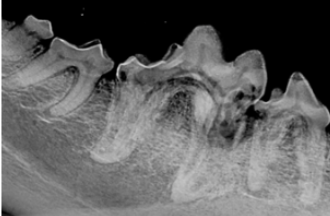

3 Dental radiographs are required for proper diagnosis and treatmentFeline tooth resorption TR a common disease in cats characterized. Internal root resorption occurs when the integrity of the outermost layer of pulp tissue is broached.

. Stage 1 These are early lesions extending less than 05mm into the tooths neck. In humans external root resorption is classified as surface inflammatory or replacement noninflammatory resorption. Histological studies have found these lesions begin on the root surface and radiographic changes can often be seen before a clinical lesion is obvious.

Tooth resorption has also been shown to occur in feral Verstraete et al. Crown amputation with intentional. The lesions are noted clinically at the cervical portion or the neck of the tooth Figure 1 or they are noted to be affecting the roots on dental radiographs.